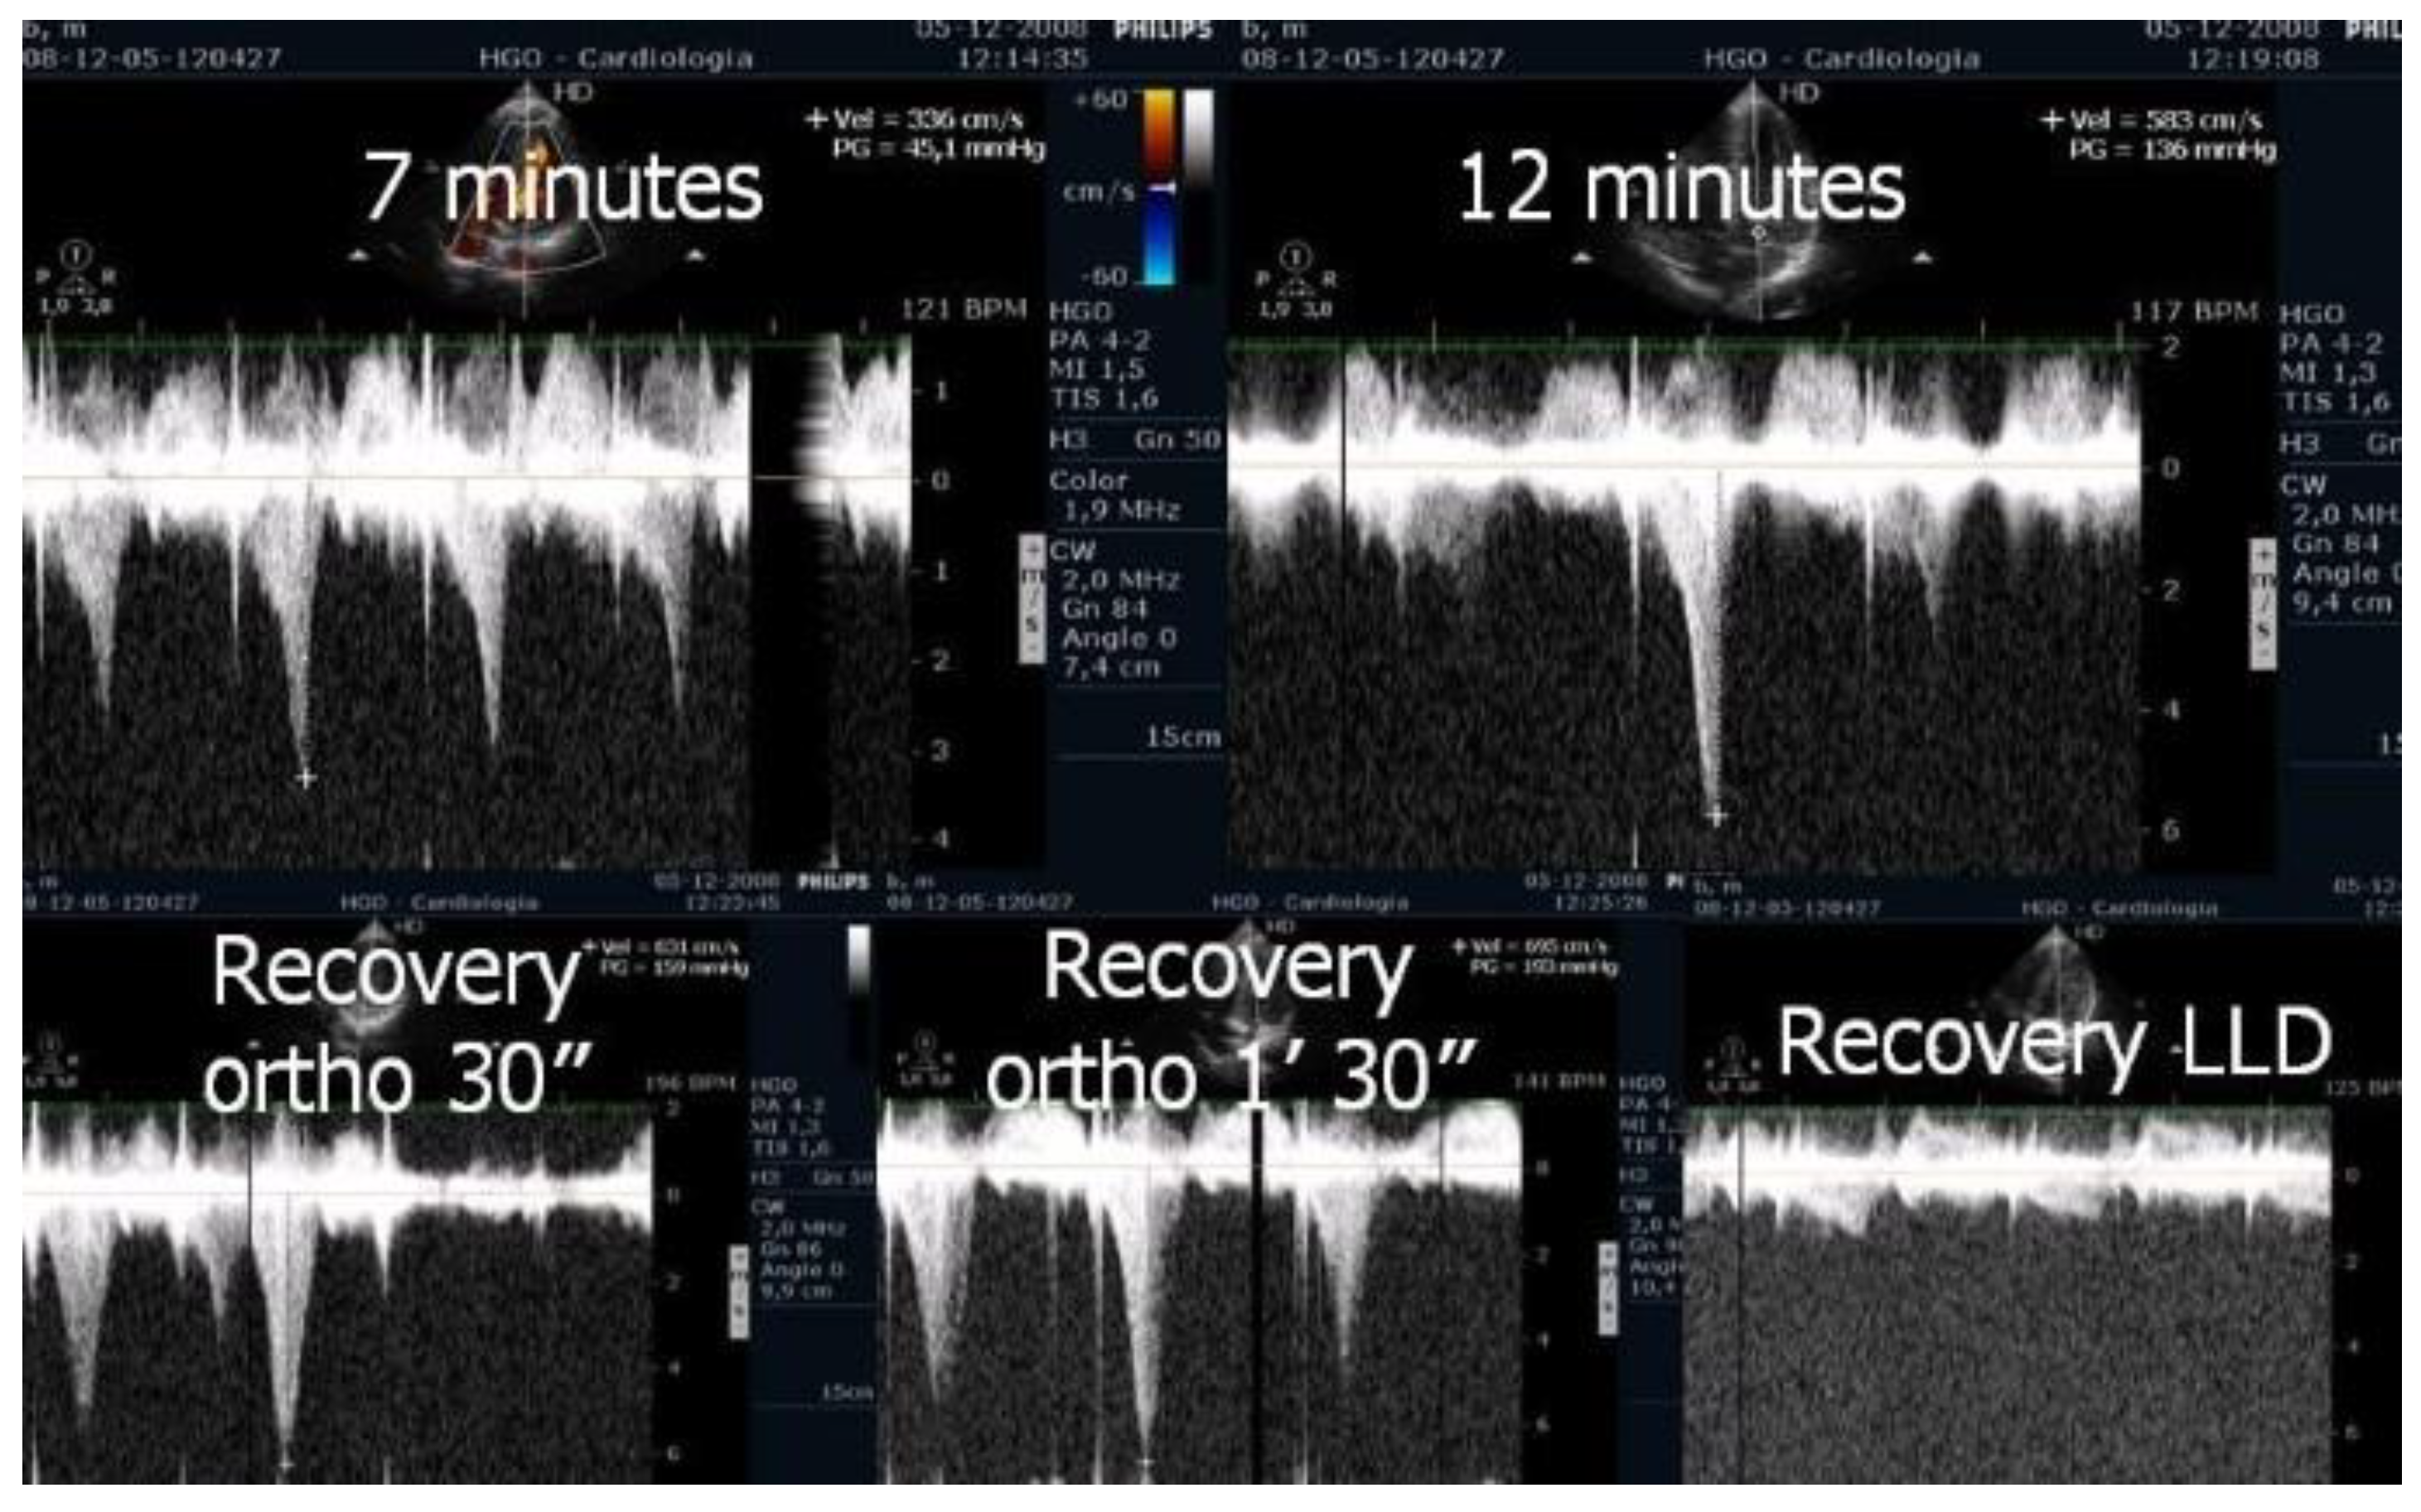

| in [1] | Evaluate IVGs with echocardiography during treadmill exercise and post-exercise in the upright position in patients with HCM. | 17 HCM | Research | Three patients with non-obstructive HCM at rest developed IVGs during exercise. One patient developed this gradient only during orthostatic recovery. The mean IVG in left lateral decubitus (LLD) was 49 ± 4 mm Hg; in orthostatic position it was 62 ± 29 mm Hg (p < 0.001 versus in LLD); at peak exercise it was 83 ± 35 mm Hg (p < 0.001 versus supine rest); during recovery it was 96 ± 35 mm Hg (p < 0.001 versus peak exercise) |